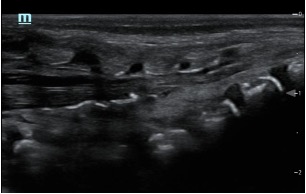

Sonoanatomy

Ultrasound probe selection: linear high frequency probe

Mapping/scout scan: look between the intervertebral spinous processes and laminae:

1)Probe position transverse over the sacral cornua (-> frog’s eyes US view)

2)Then rotate probe 90 degrees for a longitudinal view

Identify:

•Sacral cornua

•Sacrum

•Sacrococcygeal membrane

•End of the dural sac (hyperechoic (<-> CSF are anechoic (black)

•Caudal epidural space

•Assess the position of the dural sac in relation to the sacrococcygeal membrane

NOTE: Ultrasound can't see through bone; so with increasing age (= increasing angulation of the spinous processes and increasing ossification of the laminae) the size of the echo window will diminish -> you might need to scan paramedian

TIP: use a large linear probe (50mm) – this will allow you to visualise more vertebrae in one image for easier monitoring of needle approach and LA spread